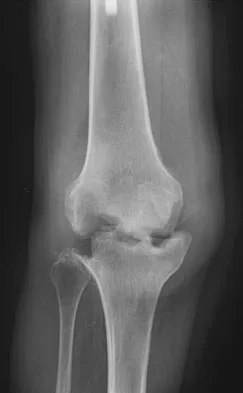

Question 369High Yield

An 82-year-old woman reports activity-related knee pain. History reveals that she underwent total knee arthroplasty 16 years ago. AP and lateral radiographs and a bone scan are shown in Figures 38a through 38c. What is the most likely diagnosis?

Explanation

The radiographs reveal a large femoral metaphyseal lytic lesion with well-defined borders. Joint space narrowing medially is consistent with polyethylene wear. The most likely diagnosis is particle-mediated osteolysis. Metastatic tumors and primary sarcomas adjacent to an arthroplasty are extremely rare. In addition, malignant tumors and infection would more likely reveal a destructive lesion with poorly defined borders and increased uptake on a bone scan. Stress shielding with massive bone loss has not been described in knee arthroplasty literature, although this entity has been observed in fully porous-coated femoral implants in total hip arthroplasty. Robinson EJ, Mulliken BD, Bourne RB, et al: Catastrophic osteolysis in total knee replacement: A report of 17 cases. Clin Orthop Relat Res 1995;321:98-105. Archibeck MJ, Jacobs JJ, Roebuck KA, et al: The basic science of periprosthetic osteolysis. Instr Course Lect 2001;50:185-195.